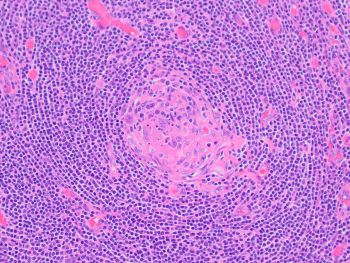

The lymph node is involved by Castleman disease, hyaline vascular variant. With disease localized to just the retroperitoneal “mass,” clinically the patient has unicentric Castleman disease. Histologically, the lymph node demonstrates a proliferation of follicles showing regressed/atretic hyalinized germinal centers with prominence of sometimes dysplastic-appearing follicular dendritic cells. There is radial penetration of germinal centers by blood vessels (so-called "lollipop" sign), and follicles with 2 or more germinal centers (so-called "twinning") are seen. There is broad expansion of mantle zones in an onion-skin appearance. The interfollicular areas contain increased thickened vessels with occasional sclerosis, occasional dysplastic-appearing follicular dendritic cells, and consists mostly of small lymphocytes with occasional transformed forms.